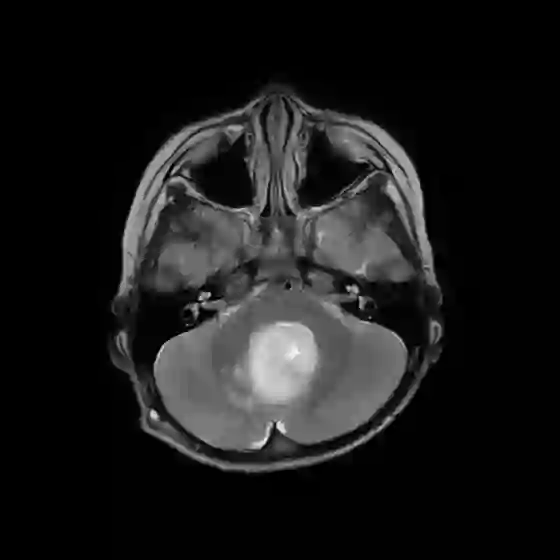

The field of explainability in artificial intelligence has witnessed a growing number of studies and increasing scholarly interest. However, the lack of human-friendly and individual interpretations in explaining the outcomes of machine learning algorithms has significantly hindered the acceptance of these methods by clinicians in their research and clinical practice. To address this, our study employs counterfactual explanations to explore "what if?" scenarios in medical research, aiming to expand our understanding beyond existing boundaries on magnetic resonance imaging (MRI) features for diagnosing pediatric posterior fossa brain tumors. In our case study, the proposed concept provides a novel way to examine alternative decision-making scenarios that offer personalized and context-specific insights, enabling the validation of predictions and clarification of variations under diverse circumstances. Additionally, we explore the potential use of counterfactuals for data augmentation and evaluate their feasibility as an alternative approach in our medical research case. The results demonstrate the promising potential of using counterfactual explanations to enhance trust and acceptance of AI-driven methods in clinical research.